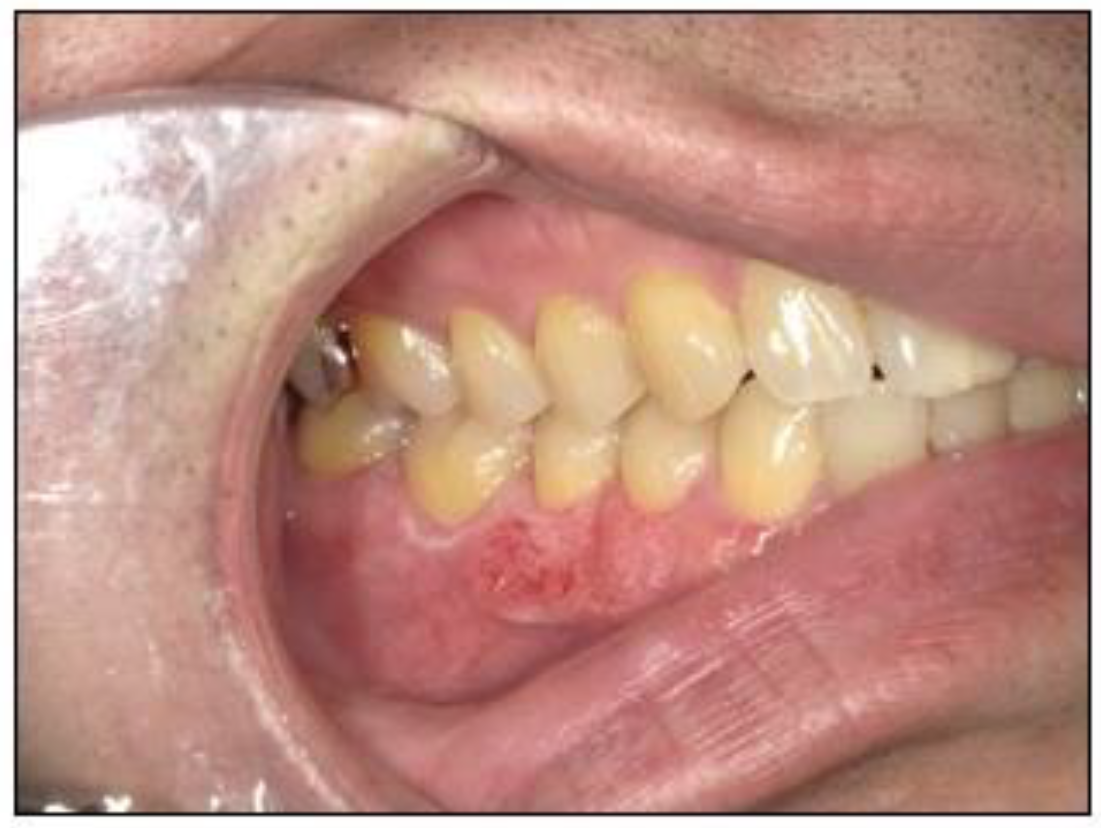

2.1. Case